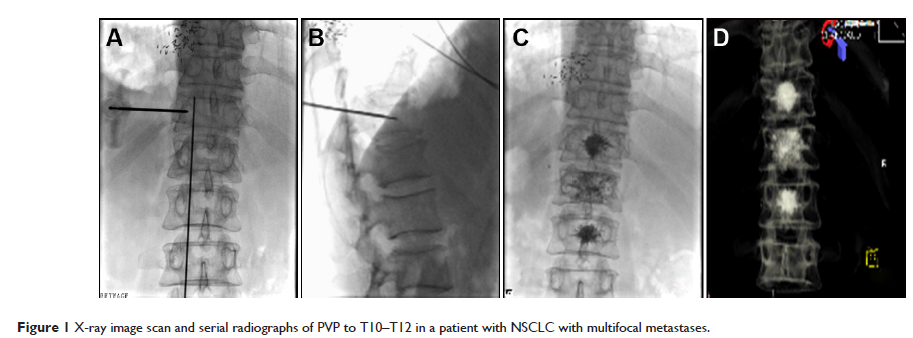

- 作者:Ying Gao, Fei Gao, Jin-lu Ma, Xiao-zhi Zhang, Yi Li, Li-ping Song, Dong-li Zhao